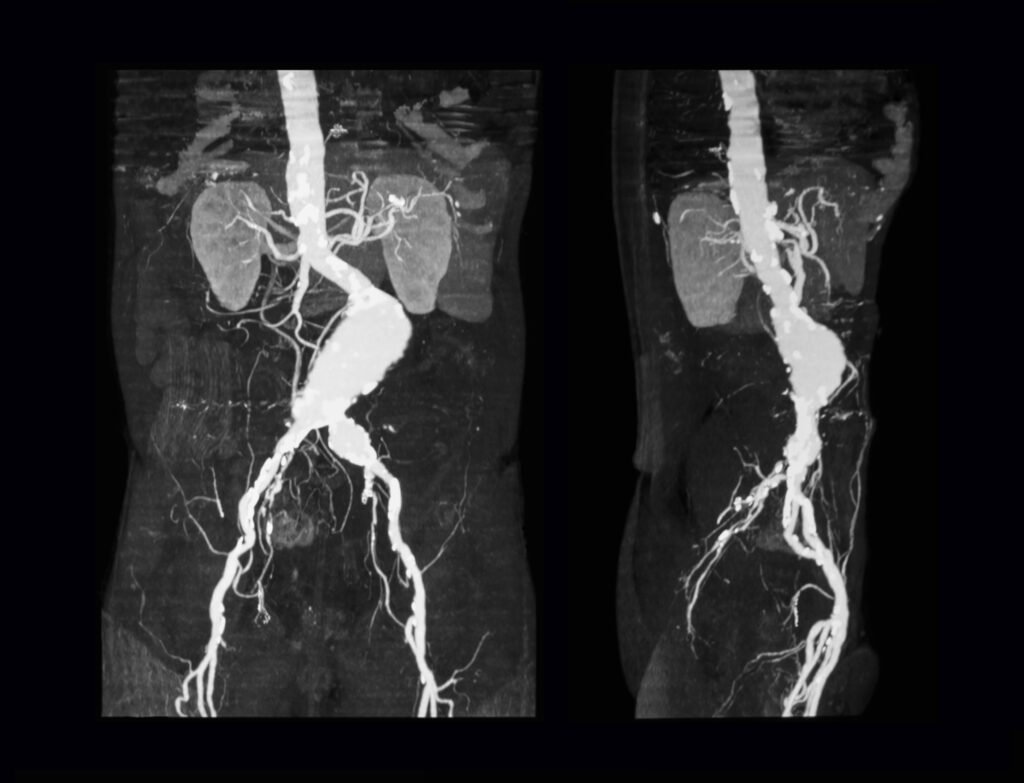

Abdominal Aortic Aneurysm (AAA) Screening. An abdominal aortic aneurysm occurs when the large blood vessel (aorta) that supplies blood to the abdomen, pelvis, and legs becomes enlarged. If an aneurysm ruptures, it can lead to life-threatening internal bleeding. AAA screening uses ultrasound to check for the presence of aneurysms in the abdominal aorta.